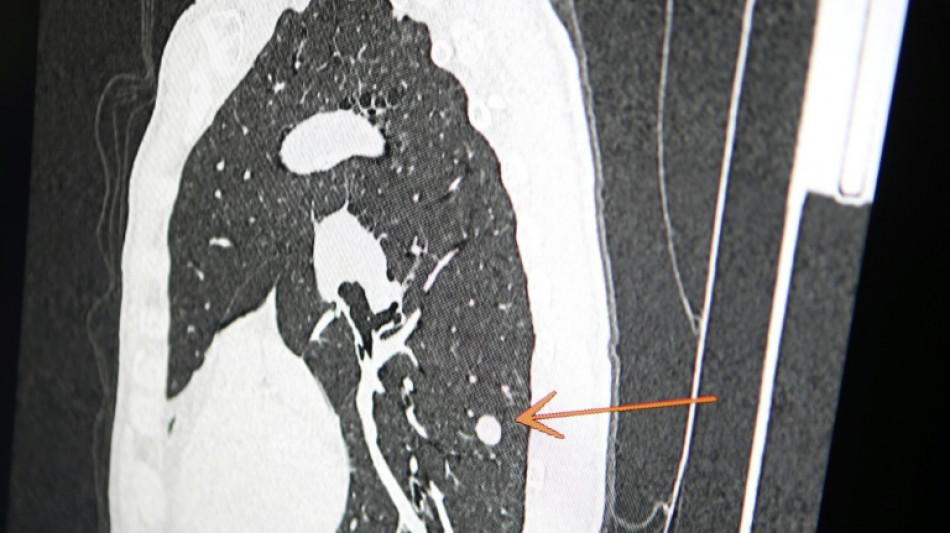

"Usted tiene cáncer", mensaje erróneo y aterrador a cientos de pacientes de una clínica en Inglaterra

"Usted tiene cáncer", mensaje erróneo y aterrador a cientos de pacientes de una clínica en Inglaterra / Foto: Pascal Pochard-Casabianca - AFP/Archivos

Una clínica del norte de Inglaterra dio un gran susto a cientos de pacientes al enviar el mensaje "diagnóstico: cáncer de pulmón agresivo con metástasis" en lugar de sus buenos deseos de Navidad, informó el diario The Sun el jueves.

El 23 de diciembre a las 15H49, los pacientes de este centro de salud de Askern, cerca de la ciudad de Doncaster, recibieron un mensaje de texto en su teléfono informándoles de este diagnóstico, pidiéndoles que rellenaran los formularios correspondientes y concluyendo: "Gracias".